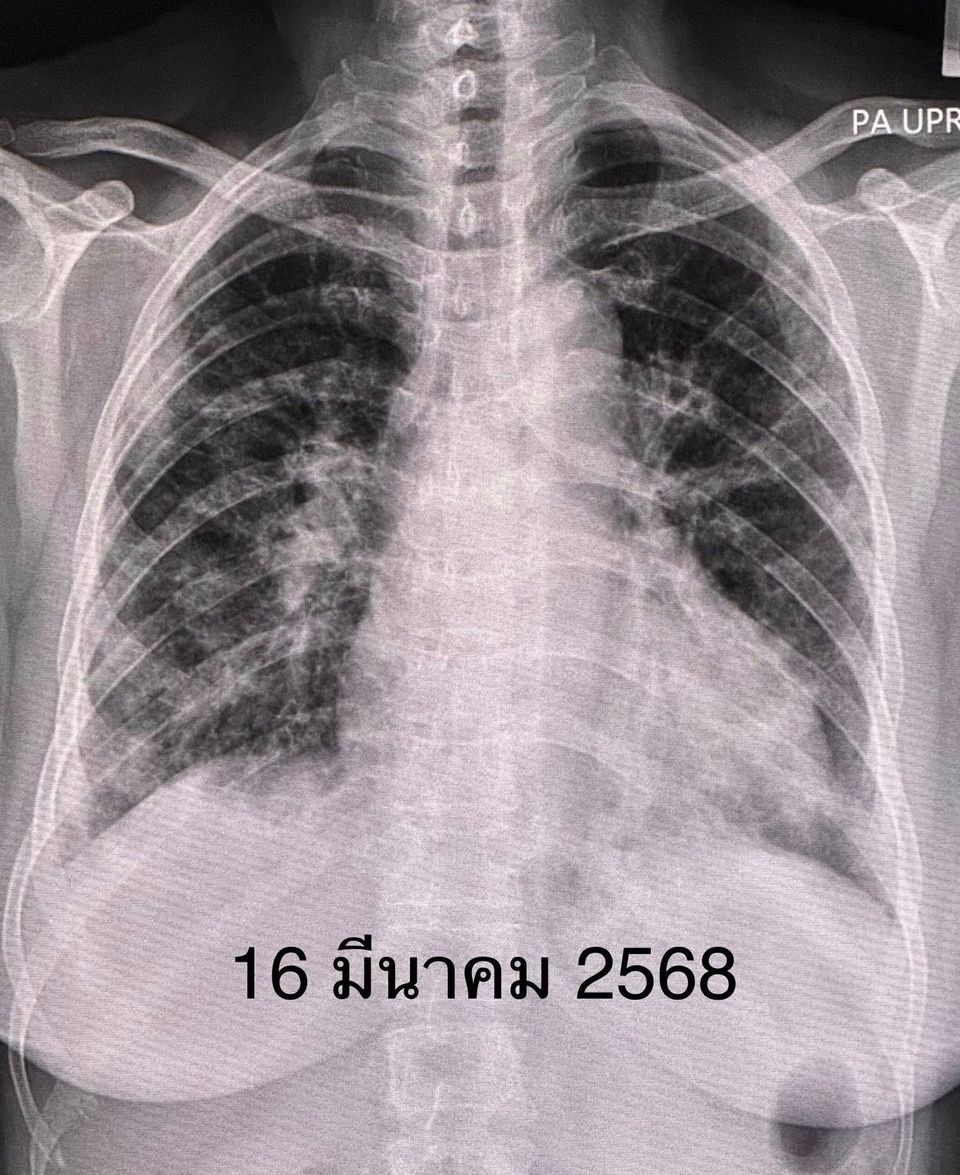

วันนี้ (29 เม.ย.68) นพ.มนูญ ลีเชวงวงศ์ แพทย์เฉพาะทางด้านระบบการหายใจและผู้ป่วยหนัก ยกเคสผู้ป่วย เพศหญิง อายุ 63 ปี เป็นโรคเบาหวาน ปกติแข็งแรงดี ไม่สูบบุหรี่ เคยติดโควิดแล้ว 2 ครั้ง เริ่มไอแห้ง ๆ เล็กน้อย และมีอาการเหนื่อยตั้งแต่วันที่ 6 มี.ค.68 เข้ารักษษที่โรงพยาบาลใกล้บ้านวันที่ 16 มี.ค.68 เนื่องจากเหนื่อยมากขึ้นจนลุกขึ้นยืนไม่ได้ ไม่มีไข้ ผิวหนังปกติ กล้ามเนื้อไม่อ่อนแรง ระดับออกซิเจนที่ปลายนิ้วต่ำมาก ต้องให้ออกซิเจนชนิดอัตราการไหลสูงทางจมูก High-Flow nasal O2 cannula

เจาะเลือด พบเลือดจางเล็กน้อย ค่าอักเสบในเลือด ESR และ hs-CRP สูง, ANA ปกติ ค่าโซเดียมในเลือดต่ำ เอกซเรย์ปอดและคอมพิวเตอร์ปอดพบปอดอักเสบทั้ง 2 ข้าง แยงจมูก ส่งเลือดเพาะเชื้อ ส่องกล้องเข้าไปในหลอดลม ไม่พบการติดเชื้อแบคทีเรีย ไวรัส เชื้อรา หรือวัณโรค ได้ยาปฏิชีวนะ เอกซเรย์ปอดซ้ำไม่ดีขึ้น หลังรักษาที่โรงพยาบาลใกล้บ้าน 26 วัน ญาติขอย้ายมารักษาต่อวันที่ 11 เม.ย.68